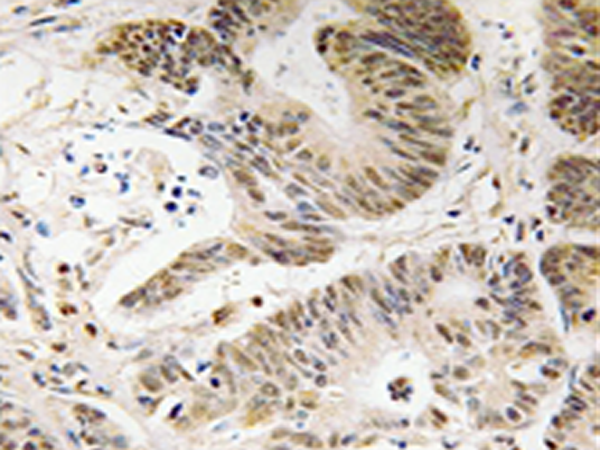

IHC positive control: |

Human colon carcinoma tissue |

IHC Recommend dilution: |

50-100 |